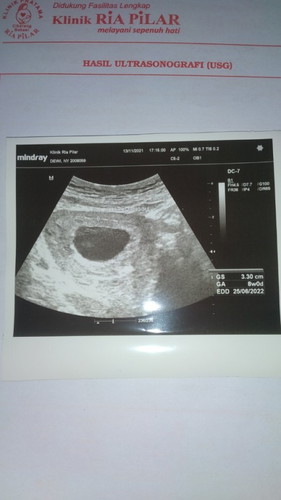

8 minggu belum terlihat janin

Bismillahirahmaanirrahiiim.. Disini adakah yg usg 8mggu belum terlihat janinnya? Gmna kata dokternya? Dan selama menunggu kontrol ulang kalian ngapain? Ngedrop bgt takut dikuret lg.. sblmnya anak ke 3 dikuret krna meninggal uk 4bln.. #bantusharing